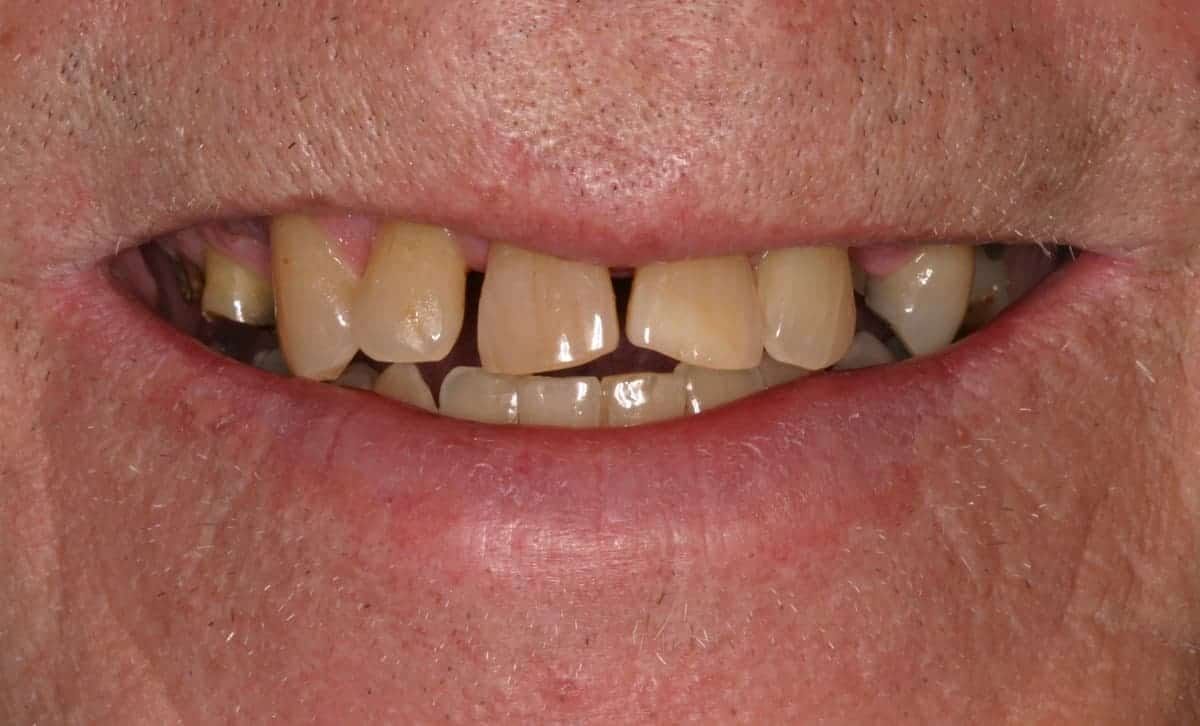

Before: Failed upper remaining teeth requiring removal. Patient elected to proceed with Phase I immediate complete denture therapy with the view toward phase II implant therapy.